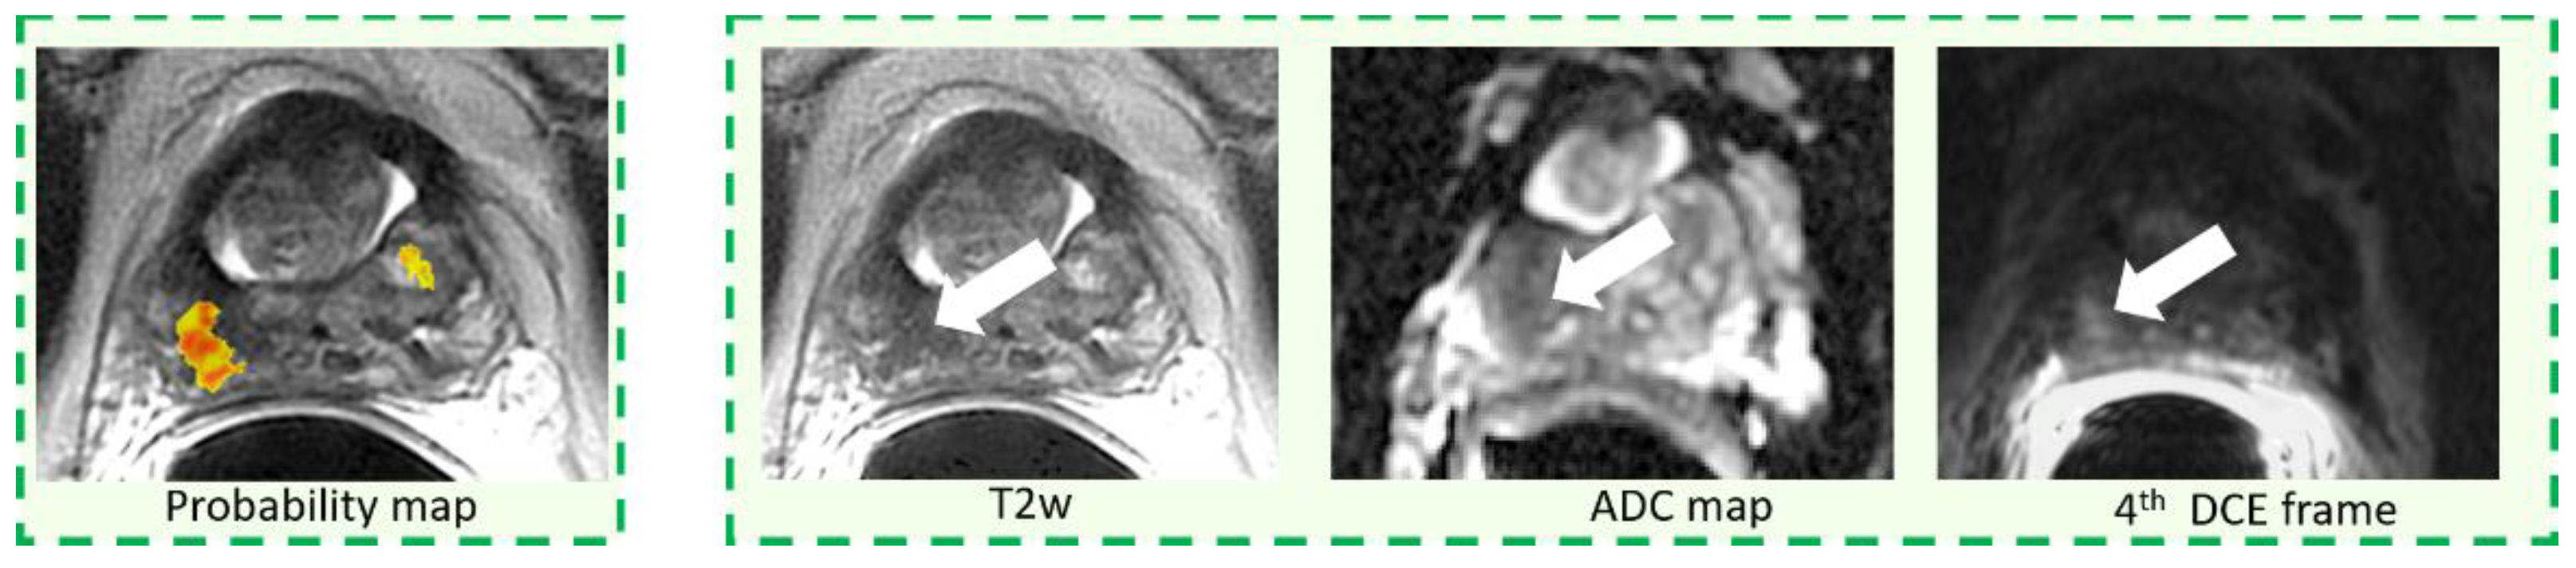

2.4. CAD System and Image Interpretation